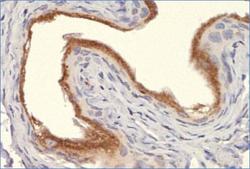

Immunohistochemistry

NB100-1974 IHC